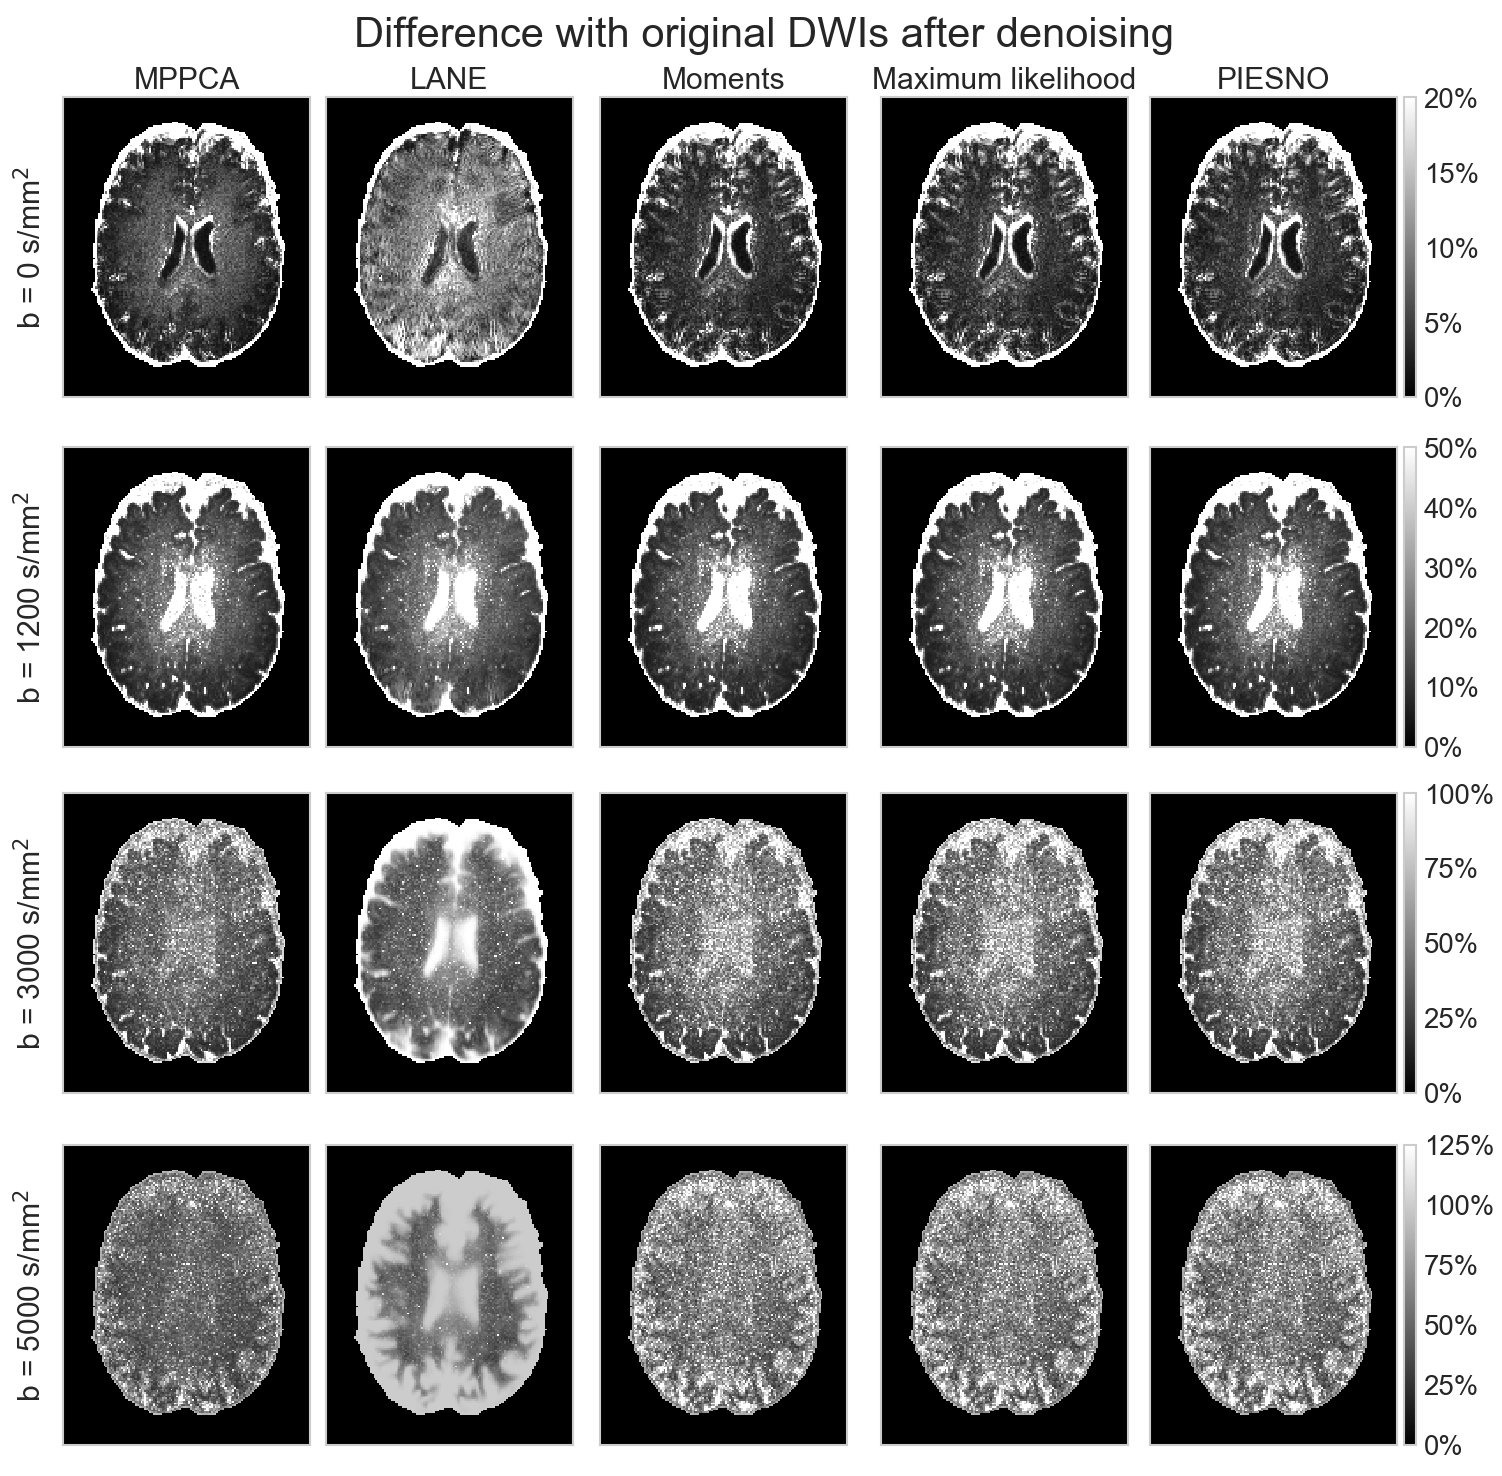

Fig. 10 shows in A) the estimated values of inside a brain mask and in B) the values of computed by the proposed methods. Estimated values of vary by an order of magnitude between the different methods. In the case of MPPCA and LANE, the median of the estimates is higher than the reference b = 5000 s/mm2 data, while PIESNO and the proposed methods estimate values lower than the reference and have lower variability in their estimated values. For the estimation of , recovered values are distributed close to 1 as is expected from an adaptive combine reconstruction providing a Rician distribution. Values estimated with the maximum likelihood equations have a lower variability than with the moments equations. In C), the top row shows the b = 5000 s/mm2 volume and spatial maps of as estimated by MPPCA and LANE. The bottom row shows voxels identified as pure noise (in light purple) using the moments, the maximum likelihood equations and PIESNO. Ghosting artifacts are excluded, but presumably affect estimation using the entire set of DWIs shown in the top row. Fig. 11 shows in A) the signal intensity after applying bias correction (left column) and after denoising (right column) for each volume ordered by increasing b-value. The top row (resp. bottom row) shows the mean (resp. standard deviation) as computed inside a white and gray matter mask. The mean signal decays with increasing b-value as expected, but the standard deviation of the signal does not follow the same trend in the cases of LANE. After denoising, the mean signal and its standard deviation decays once again as for the original data. Panel B) shows the average DWI at a given b-value for the original dataset and after denoising using the noise distribution from each method. Results are similar for all methods for the b = 0 s/mm2 datasets, but the overestimation of by LANE produces missing values in the gray matter for b = 3000 s/mm2 and b = 5000 s/mm2. In general, averaging reduces the noise present at b = 0 s/mm2 and b = 1200 s/mm2 while only denoising is effective at b = 3000 s/mm2 and b = 5000 s/mm2. At b = 5000 s/mm2, the MPPCA denoised volume is of lower intensity than when obtained by the moments, maximum likelihood equations or PIESNO. This is presumably due to LANE and MPPCA estimating higher values of than the three other methods. Finally, panel C) shows the absolute difference between the original and the denoised dataset obtained by each method. At b = 5000 s/mm2, LANE removes most of the signal in the gray matter mistakenly due to overestimating . Other methods perform comparably well on the end result, despite estimates of of different magnitude.

A)

B)

C)